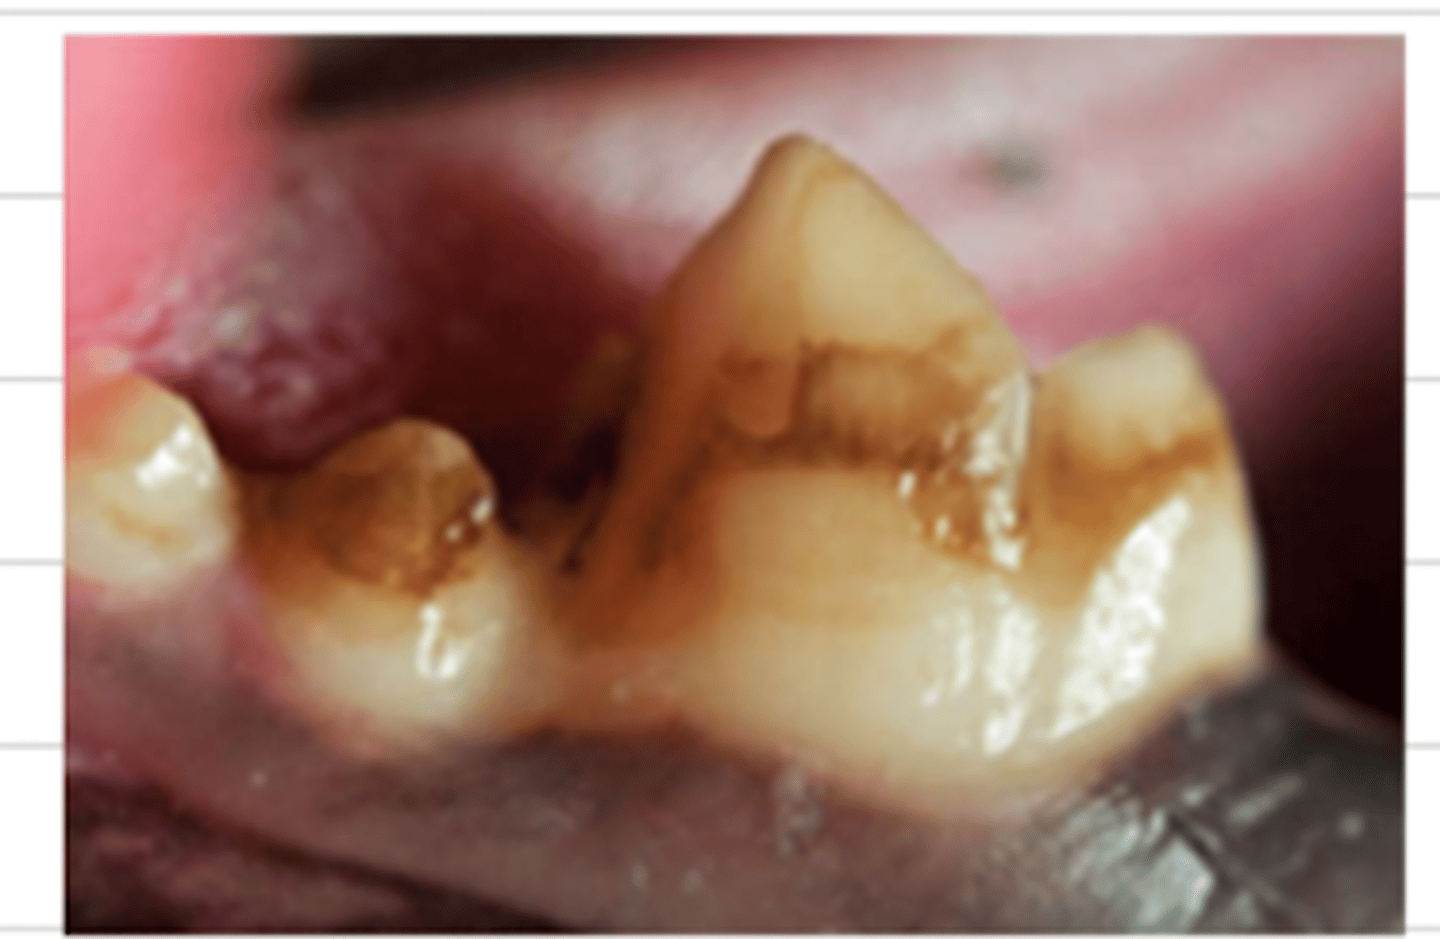

enamel problem/disorder

what is the problem?

enamel

this dog has an issue with its ______

enamel;

trauma, chemical product deposition, canine distemper virus, fever, inherited

these characteristic brown marks on the teeth indicate a problem with the ______, which can be caused by _____

it is usually unproblematic, and is just an aesthetic (appearance) issue.